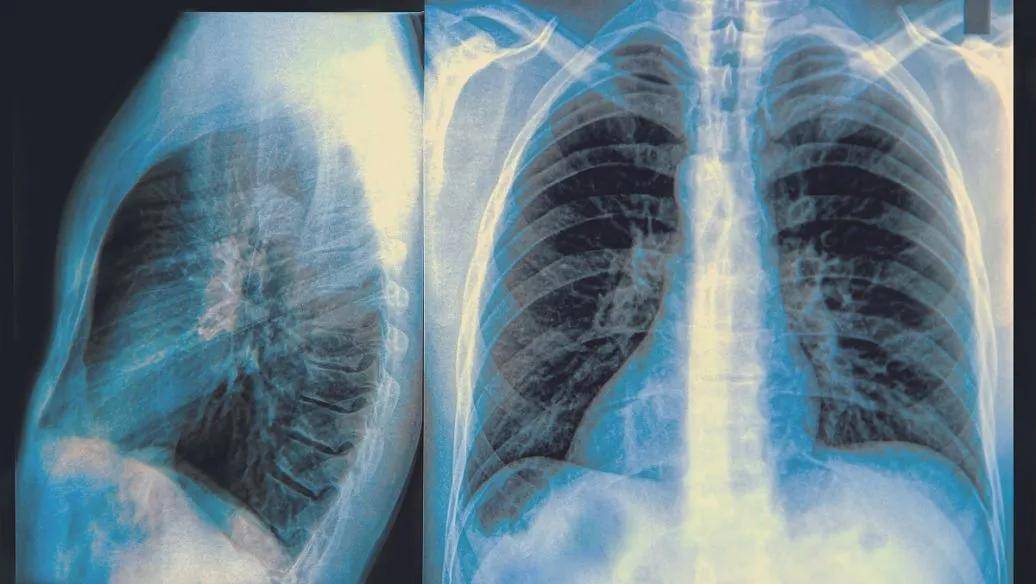

肺大疱x线

肺大疱x线,肺气肿CT

包裹性气胸or肺大泡这里有3个精彩病例

肺大泡ct